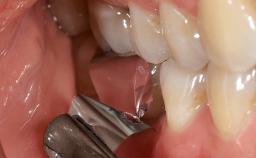

A 70-year-old female patient was referred by her general dentist to the periodontist for assessment and management of an infection associated with implant 36. The general dentist had noted suppuration on probing during examination.